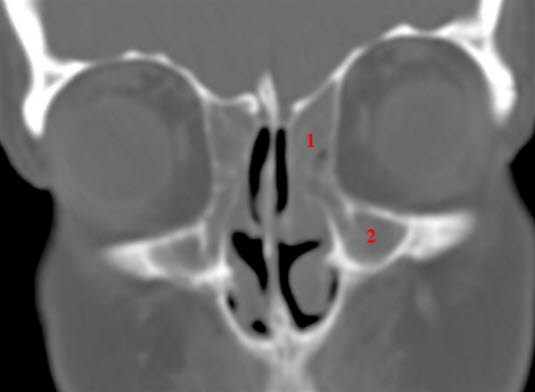

CT coronalbilde

Utfylte ethmoidalceller (1) og fremre deler av maxillarsinus (2) på begge sider